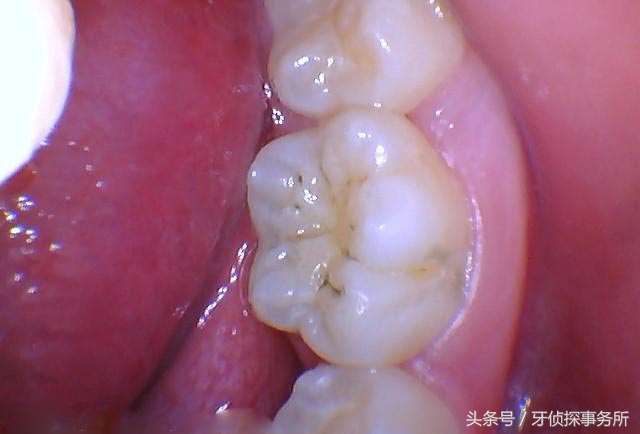

◆窝沟:窝沟是我们“大牙”表面凹凸不平的沟痕,这些沟痕能够起到增大咀嚼面积、增加摩擦力的作用,有利于把食物充分嚼碎。

◆深窝沟:深窝沟就是磨牙上面的这些沟痕裂缝比较深,食物和细菌容易嵌塞进去,且不易清洁,牙齿就容易被这些细菌侵蚀蛀坏形成蛀牙。医学上称这种蛀牙为窝沟龋。